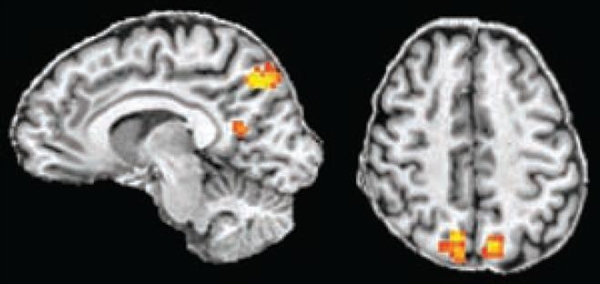

Brain scans Could Help Plan Best Treatment - Mental Healthcare

Brain scans could help brain that can be seen by MRI scan and analysed (with shorter periods of being unwell and long periods of remission) . The results of the research were published in the academic journal Psychological Medicine ... Fetch Doc